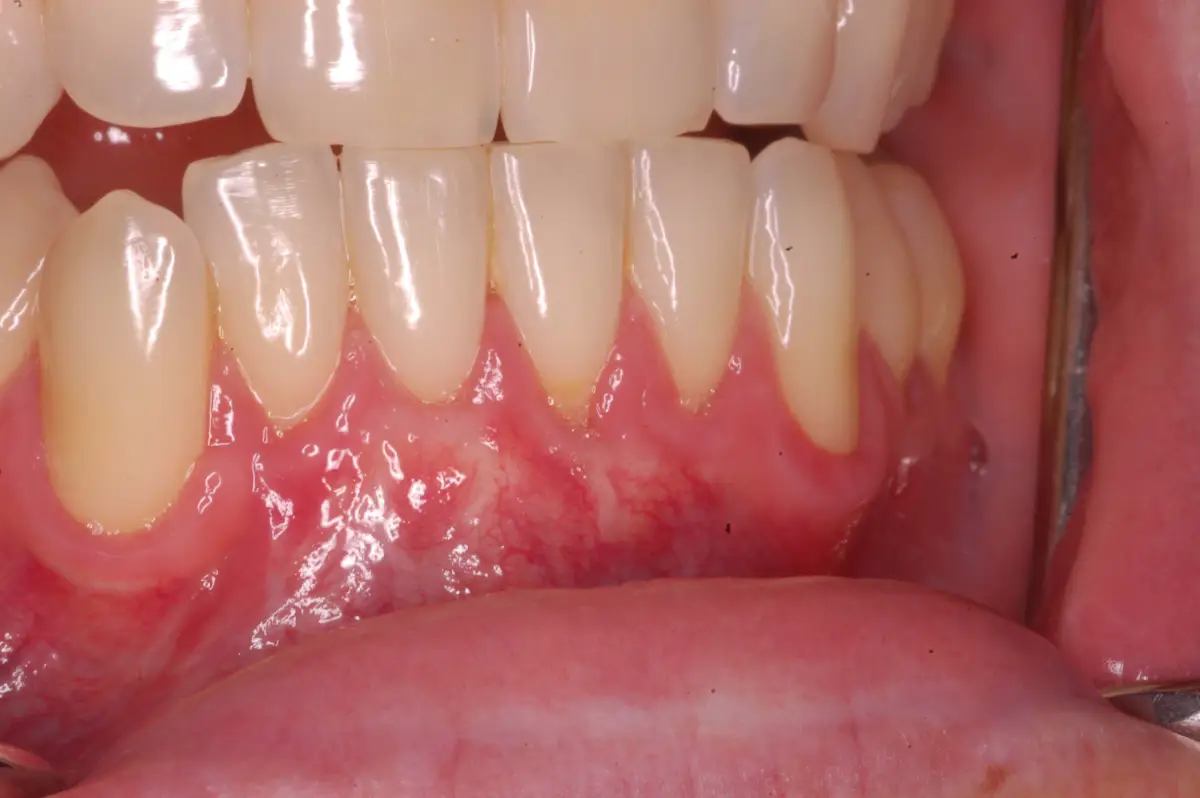

Connective Tissue Graft

before

after